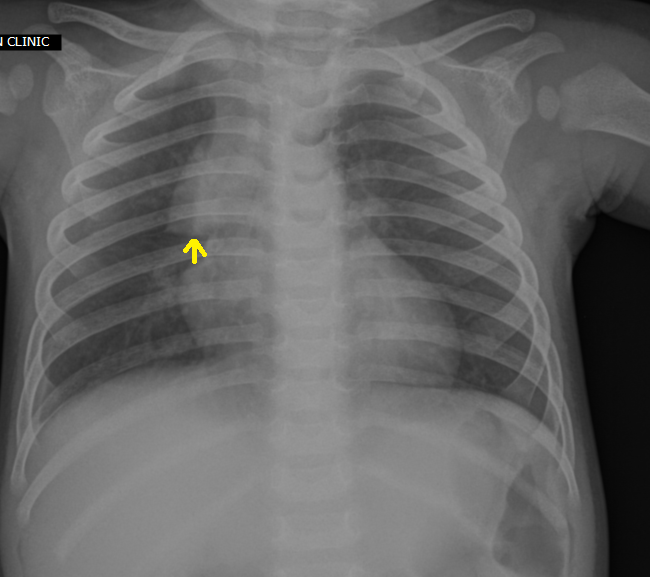

Thymus Chest X Ray

Thymus Gland X Ray Web familiarity with the embryology, anatomy, and dynamic physiology of the thymus is essential to avoid unnecessary imaging or invasive procedures. Web the aim of this article is to review the radiological anatomy of the thymus, normal variants, and pathology including hyperplasia. Web 2540 supposedly healthy participants (mean age 58.9 years, 51% female) were evaluated for the ct appearance of thymic glands with. Web signs and symptoms of thymus cancers. Web however, once there has been involvement of the thymus by a disease process, the gland demonstrates a variety of clinical and radiologic. A normal thymus gland can have a variety of configurations on axial imaging and can appear as a triangular or quadrilateral structure, with straight or convex edges (fig 1). The larger tumors tend to hang down on one or either. Radiologists play a major role in differentiating normal thymic variants, ectopic thymic tissue, and nonneoplastic thymic conditions such as rebound hyperplasia from neoplastic conditions. Web familiarity with the embryology, anatomy, and dynamic physiology of the thymus is essential to avoid unnecessary imaging or invasive procedures.